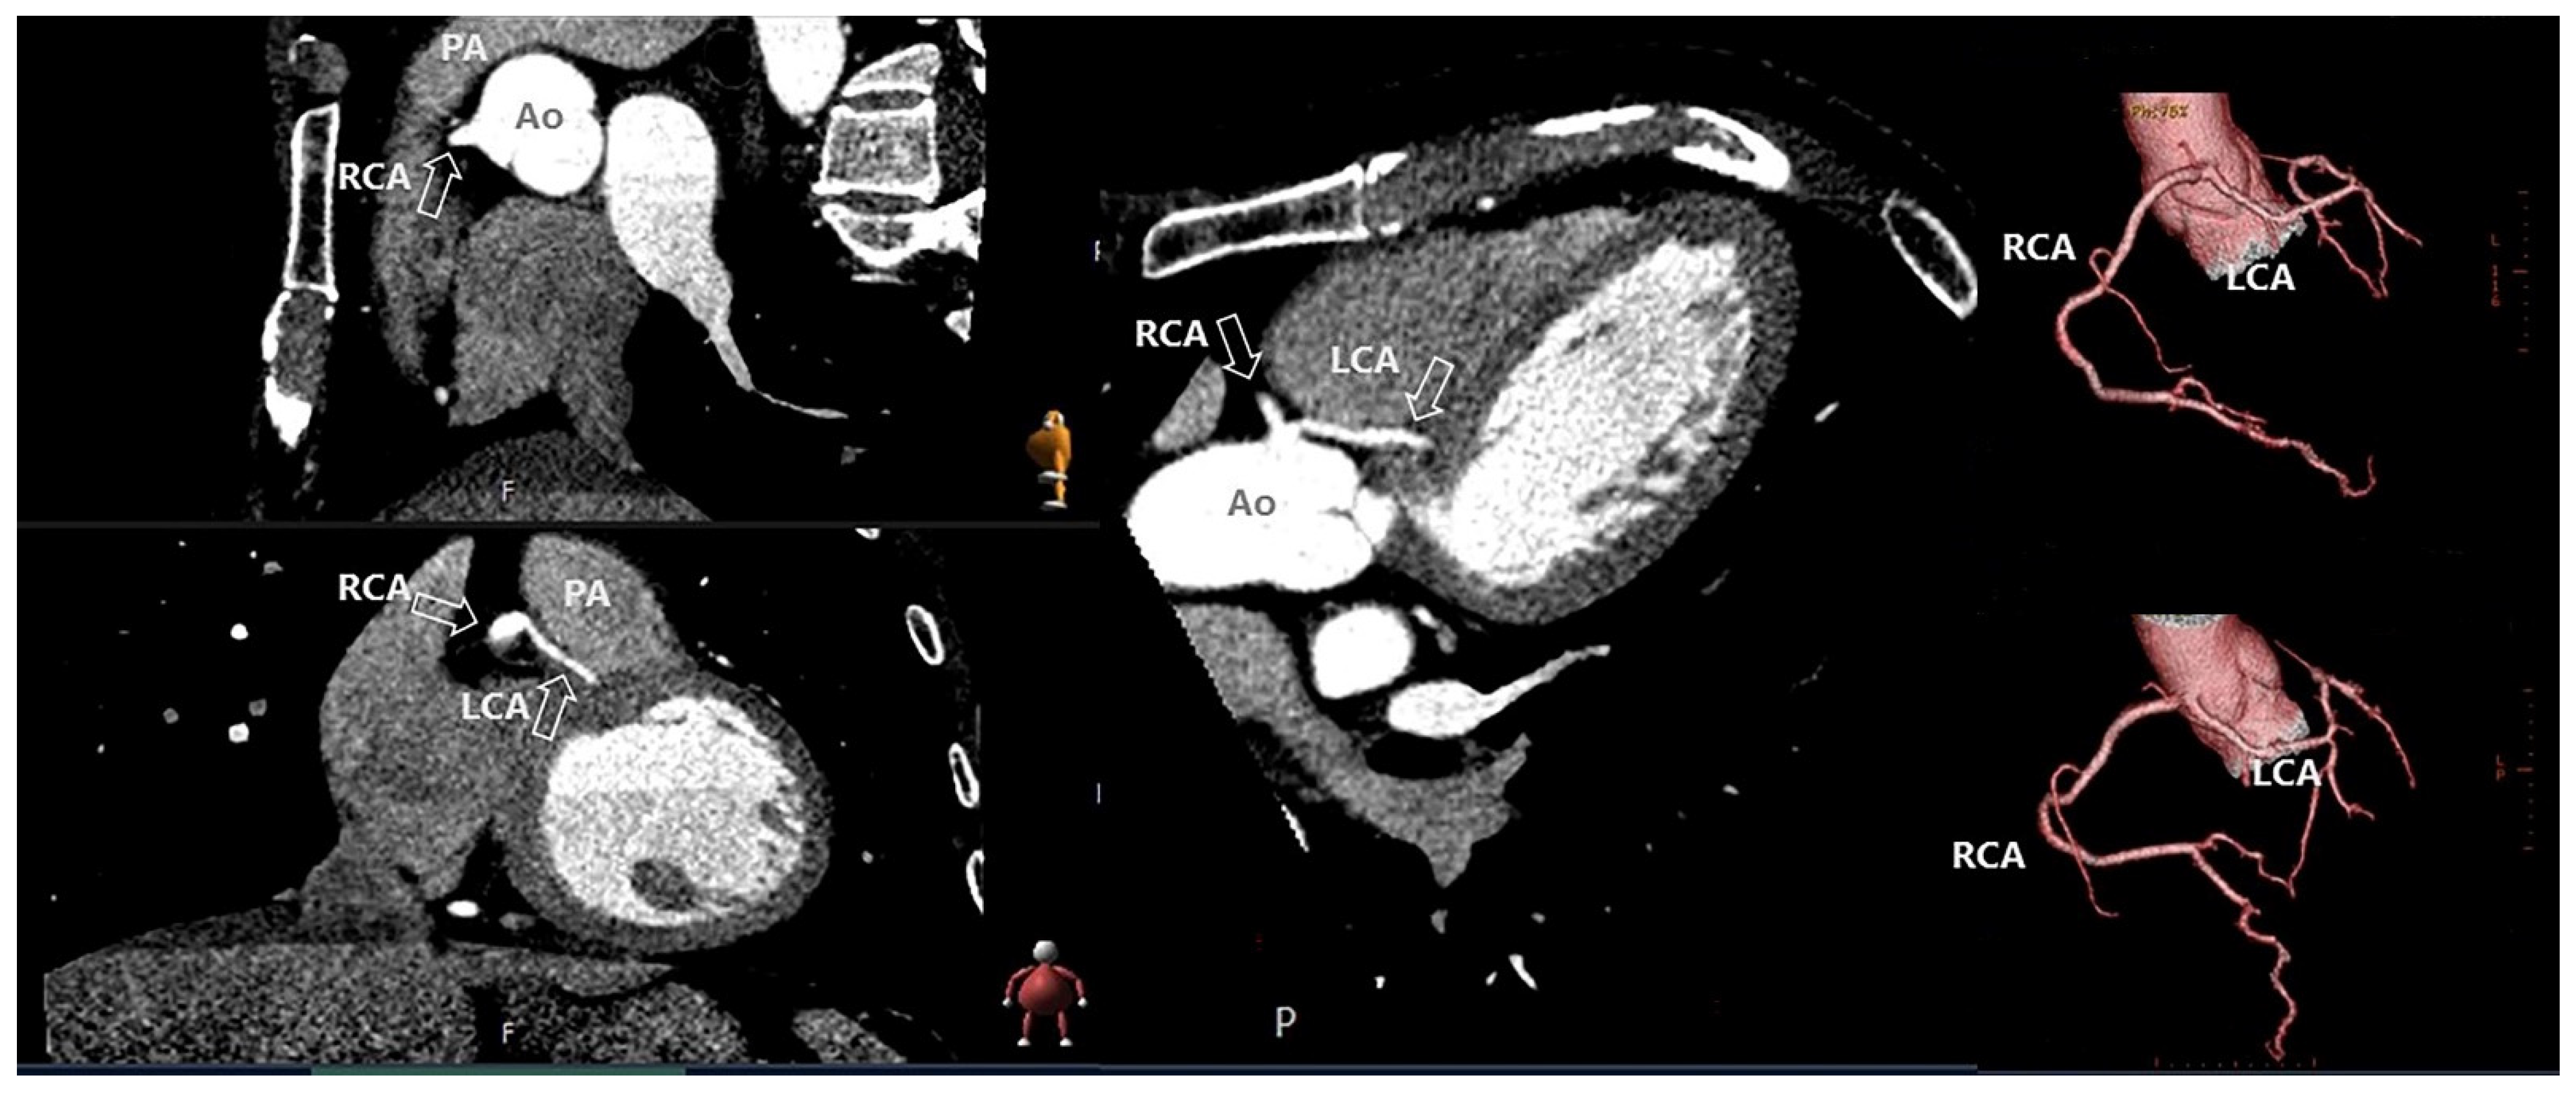

- Pontone, G.; Rossi, A.; Guglielmo, M.; Dweck, M.R.; Gaemperli, O.; Nieman, K.; Pugliese, F.; Maurovich-Horvat, P.; Gimelli, A.; Cosyns, B.; et al. Clinical Applications of Cardiac Computed Tomography: A Consensus Paper of the European Association of Cardiovascular Imaging—Part I. Eur. Heart J. Cardiovasc. Imaging 2022, 23, 299–314. [Google Scholar] [CrossRef]

- Conte, E.; Mushtaq, S.; Muscogiuri, G.; Formenti, A.; Annoni, A.; Mancini, E.; Ricci, F.; Melotti, E.; Gigante, C.; Lorenza, Z.; et al. The Potential Role of Cardiac CT in the Evaluation of Patients With Known or Suspected Cardiomyopathy: From Traditional Indications to Novel Clinical Applications. Front. Cardiovasc. Med. 2021, 8, 709124. [Google Scholar] [CrossRef] [PubMed]

- Conte, E.; Mushtaq, S.; Carbucicchio, C.; Piperno, G.; Catto, V.; Mancini, M.E.; Formenti, A.; Annoni, A.; Guglielmo, M.; Baggiano, A.; et al. State of the Art Paper: Cardiovascular CT for Planning Ventricular Tachycardia Ablation Procedures. J. Cardiovasc. Comput. Tomogr. 2021, 15, 394–402. [Google Scholar] [CrossRef] [PubMed]

- Meijboom, W.B.; Meijs, M.F.L.; Schuijf, J.D.; Cramer, M.J.; Mollet, N.R.; van Mieghem, C.A.G.; Nieman, K.; van Werkhoven, J.M.; Pundziute, G.; Weustink, A.C.; et al. Diagnostic Accuracy of 64-Slice Computed Tomography Coronary Angiography. A Prospective, Multicenter, Multivendor Study. J. Am. Coll. Cardiol. 2008, 52, 2135–2144. [Google Scholar] [CrossRef] [PubMed]

- Pontone, G.; Rossi, A.; Guglielmo, M.; Dweck, M.R.; Gaemperli, O.; Nieman, K.; Pugliese, F.; Maurovich-Horvat, P.; Gimelli, A.; Cosyns, B.; et al. Clinical Applications of Cardiac Computed Tomography: A Consensus Paper of the European Association of Cardiovascular Imaging—Part II. Eur. Heart J. Cardiovasc. Imaging 2022, 23, e136–e161. [Google Scholar] [CrossRef]

- Gräni, C.; Buechel, R.R.; Kaufmann, P.A.; Kwong, R.Y. Multimodality Imaging in Individuals with Anomalous Coronary Arteries. JACC Cardiovasc. Imaging 2017, 10, 471–481. [Google Scholar] [CrossRef]